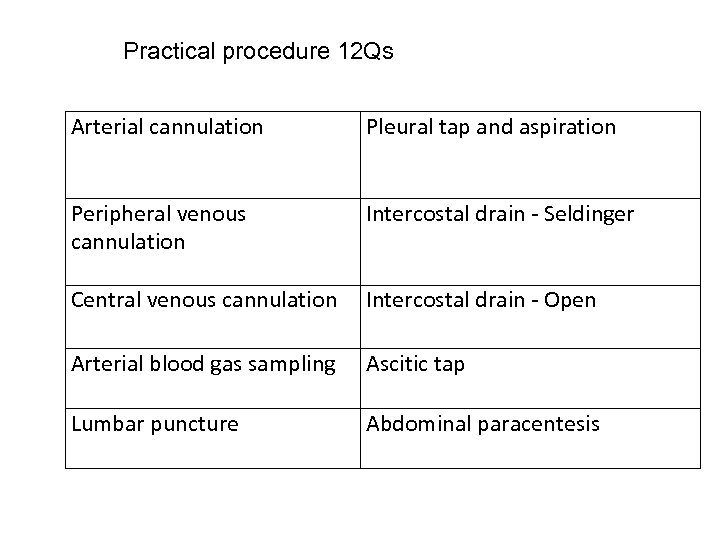

Practical procedure 12 Qs Arterial cannulation Pleural tap and aspiration Peripheral venous cannulation Intercostal drain - Seldinger Central venous cannulation Intercostal drain - Open Arterial blood gas sampling Ascitic tap Lumbar puncture Abdominal paracentesis